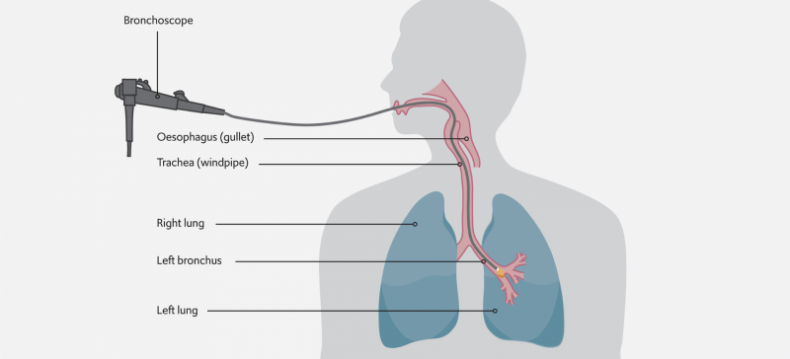

A bronchoscope with a camera at its end is used to access the cancer growth from within the lung’s airways to apply the freezing cryotherapy treatment directly to it.

Endobronchial cryotherapy uses a bronchoscope – a flexible tube-like device with a camera at its end – to reach the part of the airways affected by cancer and apply a cryogen – a substance that produces very cold temperatures between -78°C and -187°C – from its tip directly to the cancer to kill it.

“It is a short minimally invasive procedure lasting around 20 minutes and has been used for over 25 years for the effective treatment of lung cancers blocking the airways. It is a suitable option for patients with advanced lung cancer that cannot be operated on and have few other treatment options available, where it helps them to breathe better,” explains our consultant thoracic surgeon, Mr Nizar Asadi.

The freezing cryotherapy treatment kills the lung cancer cells which are then naturally removed from the body. After one or more cryotherapy treatments, the growth is completed cleared or reduced in size.

“If we manage to catch lung cancers early enough when they are small and localised to the airways, the treatment can be curative in some patients. Otherwise, it can work to reduce the size of the cancer growth so that less of the lung tissue needs to be removed during a lung resection procedure (a surgical procedure to remove part of the lung with cancer) and so ensuring lung function is preserved as much as possible.”